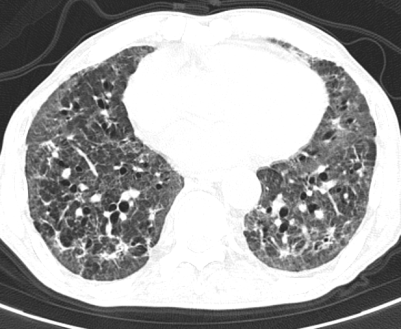

在接下来的救治过程中,挑战接踵而至。患者相继出现了血痰、血便、顽固性的低钠血症和心脏早搏等问题,治疗团队如同闯关一般,对每一个新情况都及时研判并调整用药策略。随着治疗的深入,患者的体温首先恢复正常,成为病情好转的曙光。之后的复查CT显示,肺部炎症开始逐步吸收。虽然过程中出现了肺纤维化的迹象,但通过加用抗纤维化药物尼达尼布,这一进程也得到了有效干预。

在呼吸与危重症医学科全体医护人员日以继夜的精心照护下,患者的康复之路渐渐清晰。他从完全依赖高流量吸氧,到可以尝试在床旁活动;从需要全程卧床,到能够借助鼻导管吸氧下床如厕。最终,在入院41天后,王大爷成功脱氧,能够自主缓慢行走,基本恢复了生活自理能力,顺利出院。